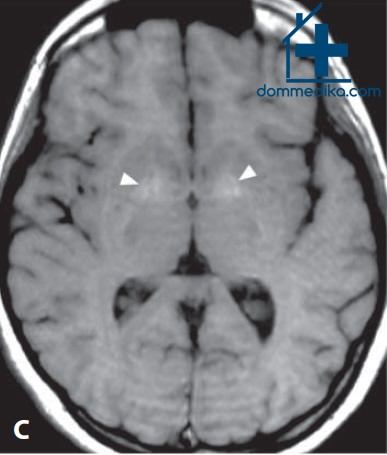

а) Специфические находки в изображениях МРТ головного мозга. Бледный шар - наиболее частое и характерное место поражения головного мозга при остром отравлении окисью углерода (СО). КТ обычно показывает симметричную гиподенсивность.

При МРТ выявляется низкий Т1-сигнал и высокий Т2-сигнал с уменьшенной диффузией. Иногда наблюдаются Т1-гиперинтенсивность и кольцо низкого Т2-сигнала, что отражает геморрагический некроз. В острой фазе возможно пятнистое или периферическое усиление сигнала после контрастирования.

Сходные изменения иногда наблюдаются при МРТ в черной субстанции, гиппокампах и коре головного мозга. У пациентов с развившейся отсроченной лейкоэнцефалопатией обнаруживаются двусторонние сливные участки высокого Т2-сигнала в перивентрикулярном белом веществе и полуовальных центрах вместе со слегка уменьшенной диффузией. Может наблюдаться также диффузное поражение белого вещества.